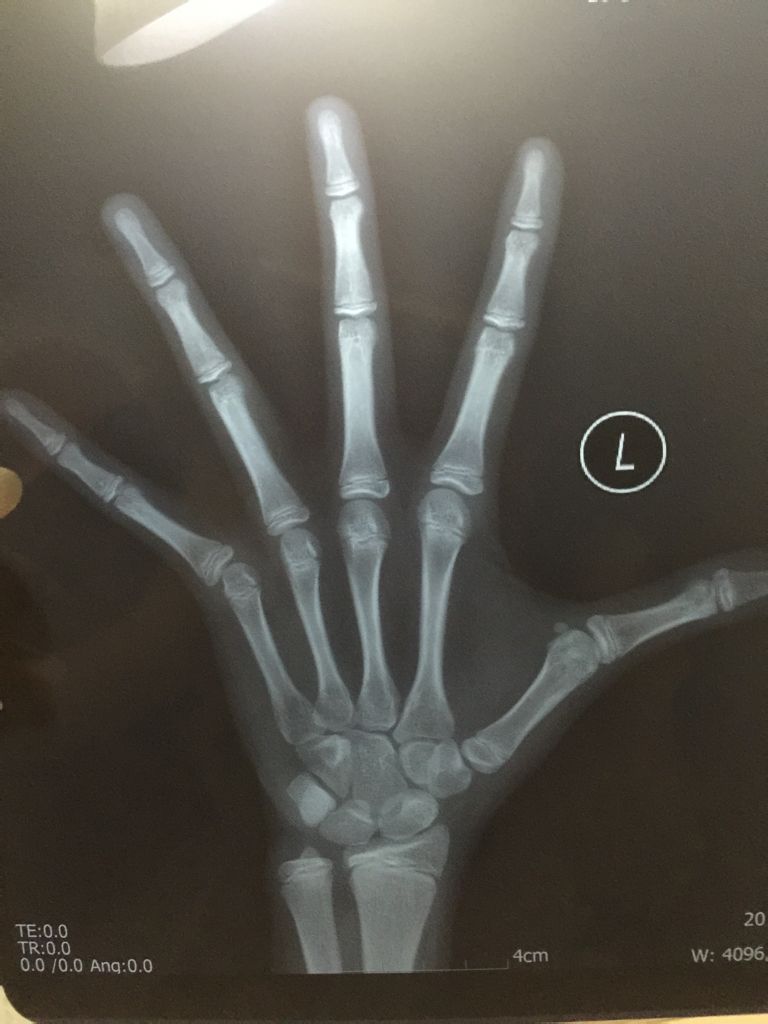

专业骨科医生请进,帮忙看下骨骺是否要闭合了?女孩10.8岁,已来初潮一月,骨龄CHN法测出骨龄已经

专业骨科医生请进,帮忙看下骨骺是否要闭合了?女孩10.8岁,已来初潮一月,骨龄CHN法测出骨龄已经12.6岁了!现在身高147,请帮忙看下不打生长素,让她自然长高,还有多长的时间能长个?